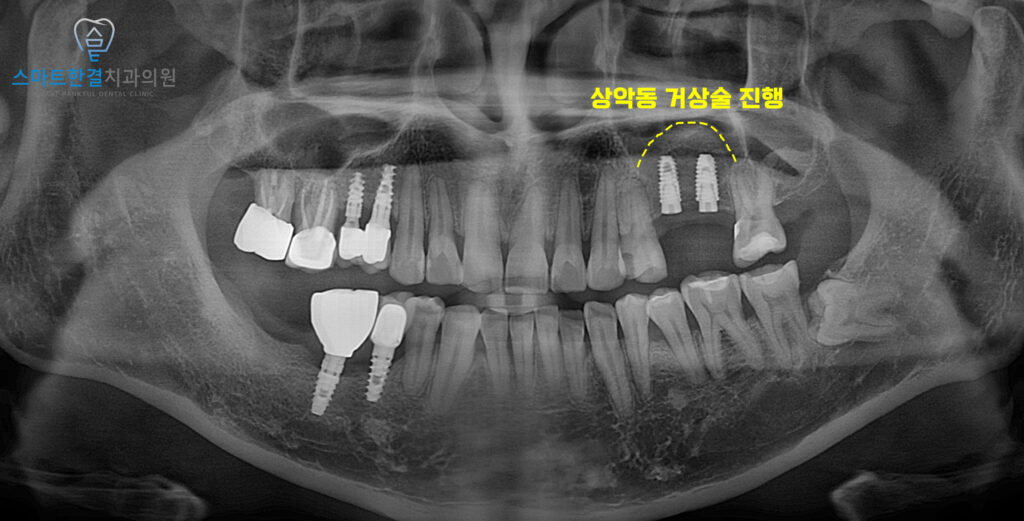

<치아 상실 후 잇몸뼈 흡수로 인해 부족>

위 환자분께서는 왼쪽 위 치아를 발치한 후,

후속 치료를 받지 않고 방치해둔 채로 계시다가

식사하기가 불편하여 기능을 회복하기 위해

본원에 내원해 주셨는데요.

확인해 보니,

발치 후 적절한 후속 치료가

이루어지지 않은 기간이 길어지면서

해당 부위의 잇몸뼈가 상당 부분 흡수된 상태였고,

특히 상악동이 아래로 확장되어

임플란트를 안정적으로 식립하기에는

뼈의 높이가 부족한 상황이었어요.

<상악동 거상술 진행>

잇몸뼈의 높이가

많이 부족한 상황이었기 때문에

측방으로 접근하여 상악동 거상술을

먼저 진행했어요.